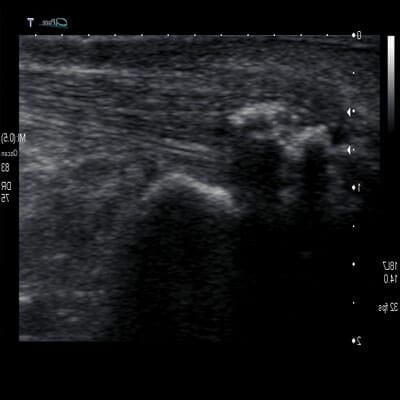

Ultrasound Guided Injection

As well as ultrasound investigation. Ultrasound can be used to ensure that injections are in the right spot which are used to minimise localised foot or ankle pain. During this procedure, a needle is inserted to deliver a small amount of substance (cortisone, glucose) into the problematic area.

Long term benefits of ultrasound guided injection therapy are seen in combination with:

- Orthotics

- Supportive shoes

- Bracing